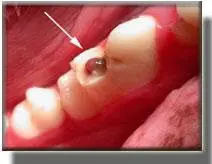

Fractured tooth with exposure of the pulp (nerve) tissue (arrow).